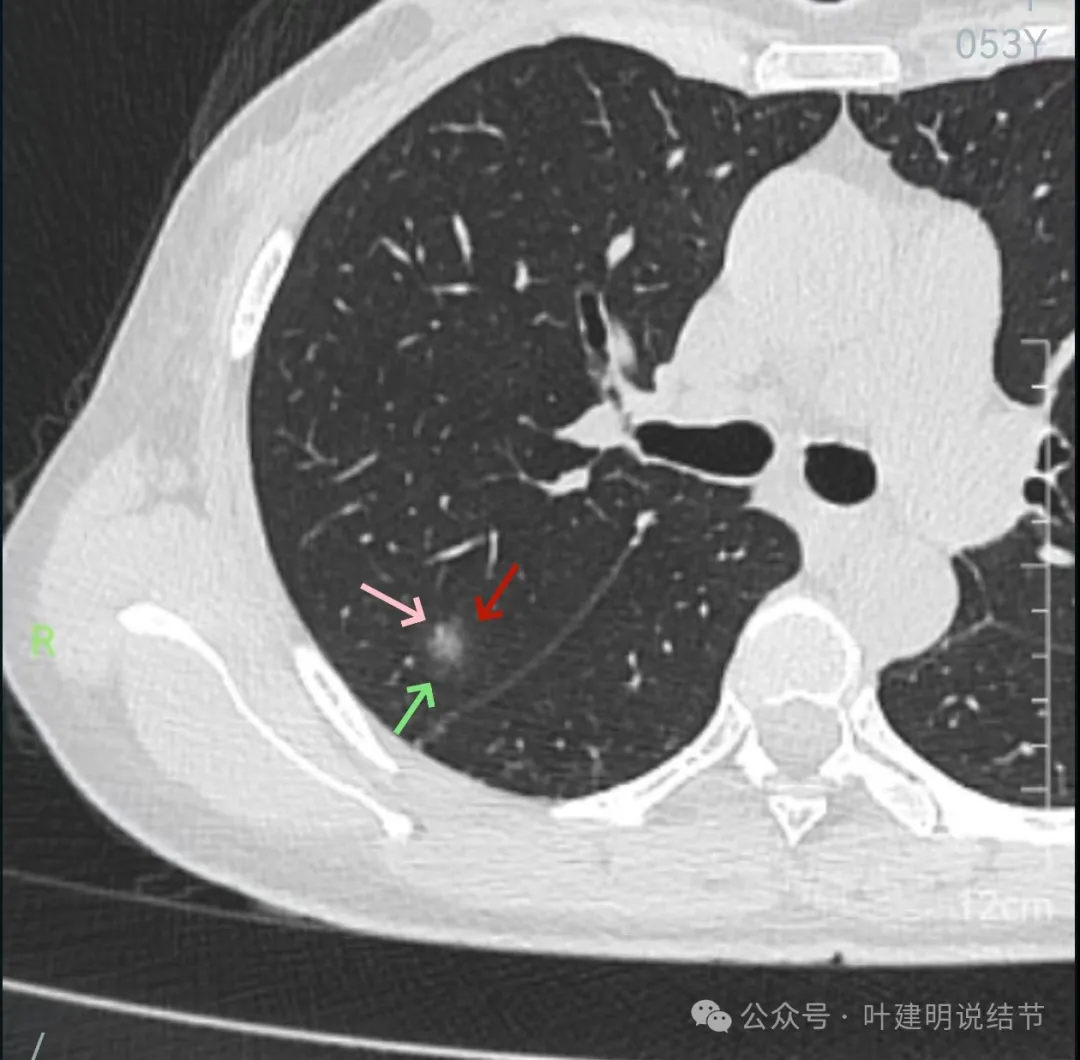

再看2024年9月27号体检时右上后段与左下最明显两处以及实性结节处的影像:

右上与左下混合密度的病灶当时都没有,实性结节是有的。

蓝色的是实性的小结节,缺乏膨胀性,两次检查都有,没有变化,考虑是良性的;红色的这些事10月份检查新增的,这两处比较明显的9月份的时候就是绿色框起来这个区域,当时是没有的。短时间内出现、多发病灶、边缘模糊、轮廓欠清,没有恶性特征,与炎性病变符合。建议查查隐球菌方面的化验,如此结果阳性,请呼吸内科或感染科处理。意见供参考!

矢状位上看,病灶虽整体轮廓较清,但瘤肺边界显模糊,整体不致密。

冠状位上看病灶有实性成分,实性成分缺乏收缩力,外围是淡磨玻璃成分,瘤肺边界欠清,贴着叶裂没有影响。